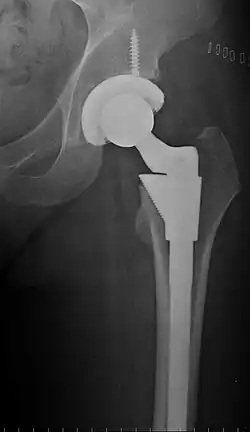

Post-operative projectional radiography is routinely performed to ensure proper configuration of hip prostheses.

The direction of the acetabular cup influences the range of motion of the leg, and also affects the risk of dislocation.[20] For this purpose, the acetabular inclination and the acetabular anteversion are measurements of cup angulation in the coronal plane and the sagittal plane, respectively.

Acetabular anteversion.[105] This parameter is calculated on a lateral radiograph as the angle between the transverse plane and a line going through the (anterior and posterior) margins of the acetabular cup.[105]

Center of rotation: The horizontal center of rotation is calculated as the distance between the acetabular teardrop and the center of the head (or caput) of the prosthesis and/or the native femoral head on the contralateral side.[104] The vertical center of rotation instead uses the transischial line for reference.[104] The parameter should be equal on both sides.[104]